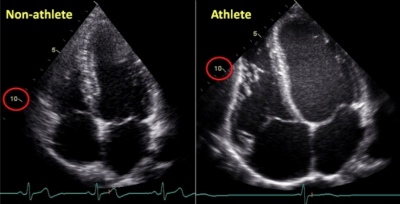

Изменение геометрии сердца у спортсменов, в зависимости от пола.

Изменение геометрии сердца у спортсменов, в зависимости от пола.У большинства высококвалифицированных спортсменов отмечается нормальная геометрия ЛЖ...